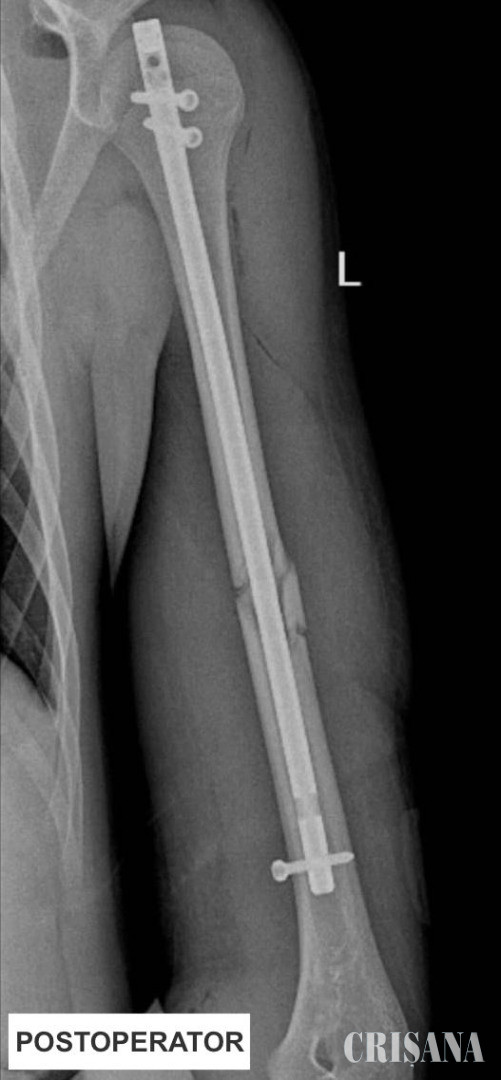

Așadar, echipa operatorie a decis să efectueze, în premieră județeană, reducerea ortopedică închisă cu osteosinteză prin tijă zăvorâtă din titan pentru un pacient pediatric. Sub control radiologic, s-a efectuat reducerea ortopedică închisă a osului fracturat, iar apoi s-a introdus o tijă de titan pentru fixarea fragmentelor osoase.

Primul pas a presupus repunerea la loc a celor două fragmente ale osului fracturat. Cu ajutorul unor truse speciale și a ghidajului radiologic, chirurgii au introdus tija pentru a asigura poziția osului fracturat. Acest abord a presupus efectuarea de radiografii repetate în timpul intervenției pentru a se vedea unde este tija și cât de aproape este de focarul de fractură. După poziționarea acesteia pe os, următorul pas a fost montarea a 3 șuruburi pentru ancorarea tijei în humerus. Tija de titan este de calibrul canalului medular, având dimensiuni de 28 cm lungime 8 phi în diametru. Intervenția a fost una de complexitate ridicată, humerusul fiind un os foarte greu de redus. Operația a avut loc în data de 20 aprilie, a durat o oră și jumătate și a decurs bine.